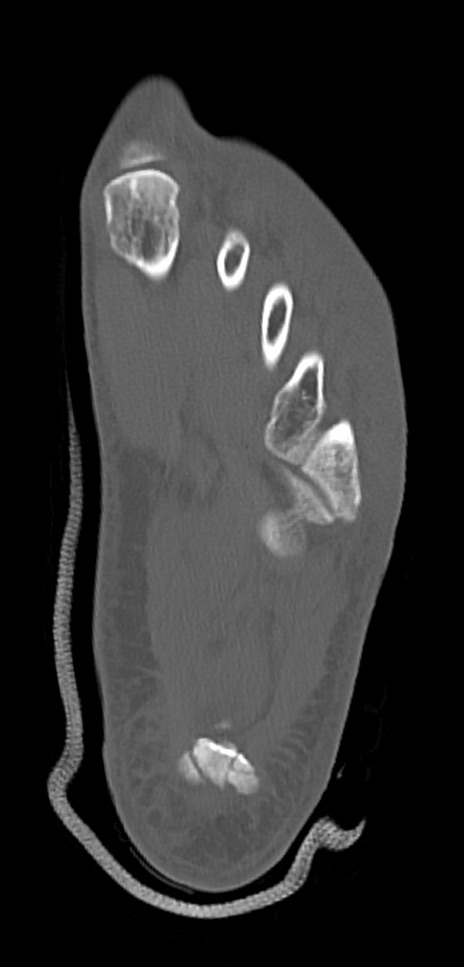

左足関節CT

矢状断像